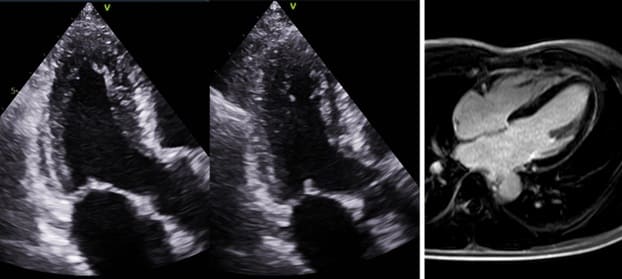

การตรวจประเมินหลอดเลือดหัวใจชนิดไม่รุกราน (Non Invasive) ได้รับความนิยมเพิ่มขึ้น ทั้งการทำ Stress Echocardiography, Stress Cardiac Magnetic Resonance Imaging (Stress MRI) และ Coronary Computed Tomographic Angiography (CCTA) ซึ่งสามารถคัดกรองผู้ป่วยที่มีผลการตรวจปกติหรือผิดปกติเพียงเล็กน้อยออกไป โดยไม่จำเป็นต้องไปถึง การฉีดสีสวนหัวใจ (Coronary Angiography: CAG) ซึ่งเป็นการตรวจชนิดรุกราน (Invasive) และมีภาวะแทรกซ้อนมากกว่า แต่ในกรณีที่ผลการตรวจผิดปกติชัดเจนมักจะนำไปสู่การฉีดสีสวนหัวใจ ซึ่งเป็นมาตรฐานในการวินิจฉัยโรคหลอดเลือดหัวใจ

ภาพจากการตรวจ stress echocardiograpphy (ซ้าย) และ การตรวจคลื่นแม่เหล็กไฟฟ้า (cardiac magnetic resonance imaging : MRI) (ขวา)